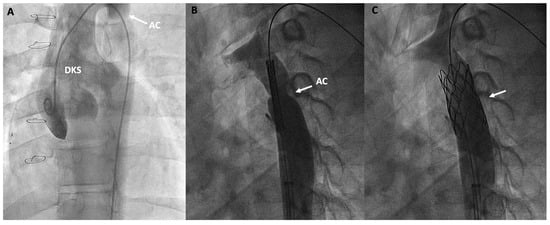

3.5.4. Aortic Coarctation Repair

| Aortic Coarctation | Balloon angioplasty and, more frequently, stent implantation can be used to repair aortic arch and aortic coarctations, which can compromise Fontan circulation. |